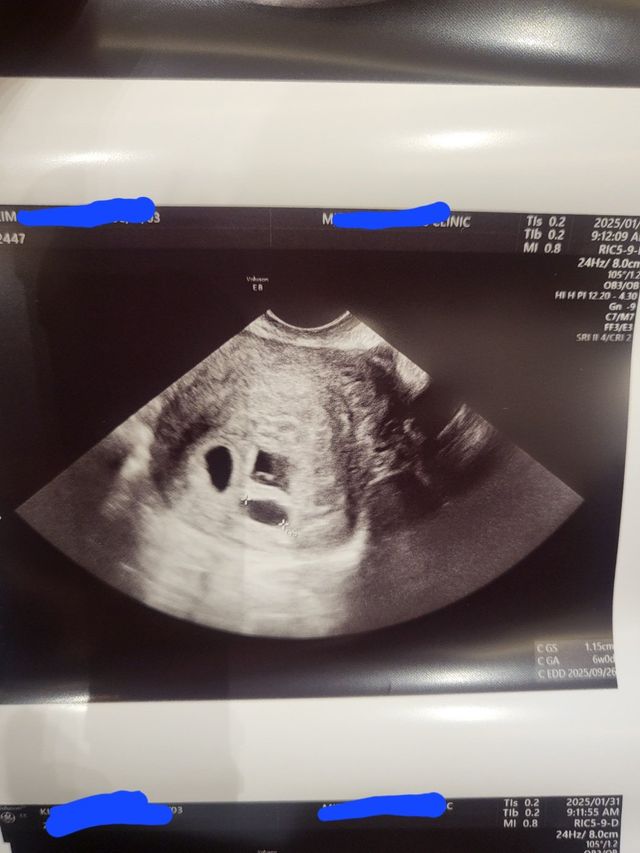

시험관 10회차 만에 드디어

임신 성공 !!!!!!!!

인데

세쌍둥이네요... 와이프 너무너무 고생해서